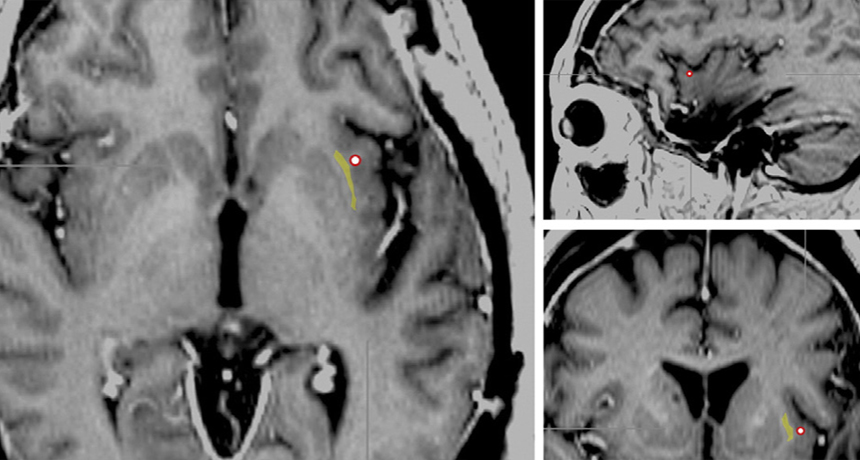

OFF SWITCH An electrode (red circle) used to stimulate a brain site near an epileptic woman’s claustrum (highlighted in yellow) appears on these brain scans. When the electrode was turned on, she appeared to lose consciousness.

M. Koubeissi et al/Epilepsy & Behavior 2014

The abrupt switch from awareness to its complete absence may be orchestrated by an enigmatic wisp of brain tissue known as the claustrum, scientists propose June 24 in Epilepsy & Behavior. The consciousness-impairing electrode was positioned close to this thin sheet of cells, which forms connections with many other regions of the brain.

While undergoing treatment for severe epilepsy, a 54-year-old woman had multiple electrodes inserted into her brain. Koubeissi and his colleagues were surprised by a big change when they turned on the electrode near the claustrum.